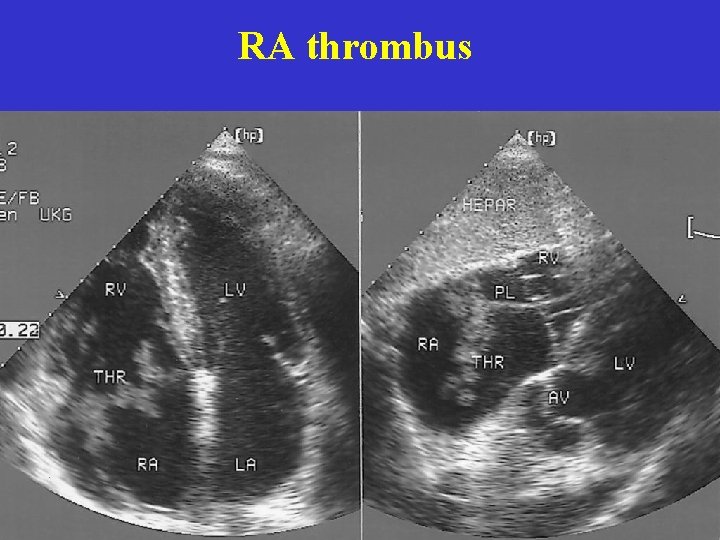

RA thrombus

Massiva PE, TTE Goldhaber SZ, NEJM, 1998